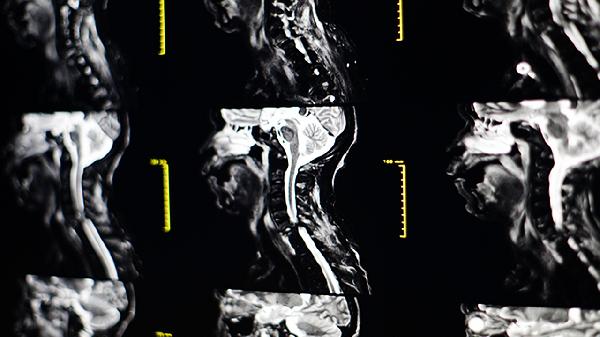

颈椎间盘突出或骨质增生可能压迫神经根,引发颈部肌肉反射性痉挛。这类疼痛常向肩臂放射,可能伴有手指麻木。需通过颈椎MRI明确诊断,治疗包括颈椎牵引、红外线理疗。药物可选择颈复康颗粒、洛索洛芬钠片、甲钴胺分散片等,严重者需考虑椎间孔镜手术。